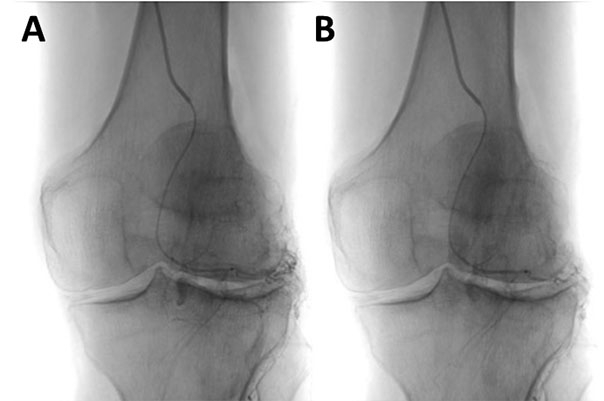

Kniegelenk